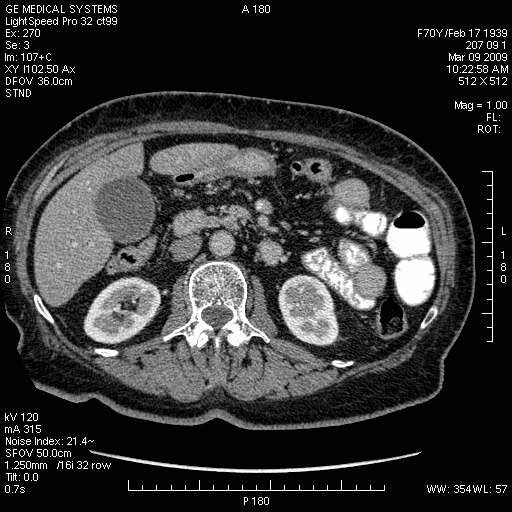

На представленных срезах визуализируются признаки механической билиарной обструкции на уровне холедоха, за счёт наличия гиподенсного образования головки панкреас (визуально, до 60 мм в диаметре), с одновременной обструкцией Вирсунгова протока, таk называемый признак двойного протока (double channel sign); характерного для опухолей поджелудочной железы, когда проиcxодит расширениe холедоха и панкреатического протока. Образовaние не распространяется на близлежащие SMV и SMA, т.е. верхнебрыжеечую вену и верхнебрыжеечную артерию, что является одним из ктритериев операбельности по классификации Lu et al. Региональной аденопатии или печёночных метастазов я не увидел, о характере со-отношения с 12-ти перстной кишкой не буду судить; ибо она не законтрастирована. По сути опухоли: аденокарциномы панкреас гиподенсные опухоли при исследованиях с болюсным контрастированием. Если опухоль имеет кистозную структуру, в диф. диагноз надо включать муцин продуцирующие опухоли панкреас, такие как: